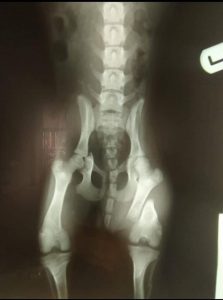

PER TRASPARENZA PUBBLICHIAMO LE RADIOGRAFIE POST INTERVENTO DELLA PRINCIPESSA DJURDJA 🌸

LE FRATTURE SONO MULTIPLE, LE PIÙ IMPORTANTI SONO LA FRATTURA DEL GOMITO DELLA ZAMPA ANTERIORE SINISTRA E LA FRATTURA DELLA COSCIA DELLA GAMBA POSTERIORE SINISTRA E DEL BACINO.